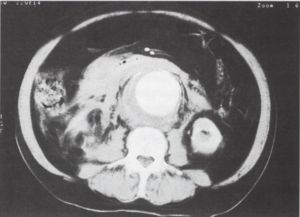

7. ábra.

Az aorta csaknem teljes egészében halmozza a kontrasztanyagot, csak jobb oldalon látszik diszkrét sarló alakú hipodenz sáv (a thromobus cranialis vége). A lép és a máj kontrasztanyag halmozása csekély. Bal oldalon, a pleuraűrben sarló alakú folyadékgyülem (*).

8. ábra.

A pancreas corpus síkjában, az a. mesenterica superiror eredése alatt az aorta nem, a v. cava inferior kifejezetten halmozza a kontrasztanyagot. A jobb vese hipodenz maradt, a megkisebbedett bal vese halmozza a kontrasztanyagot.